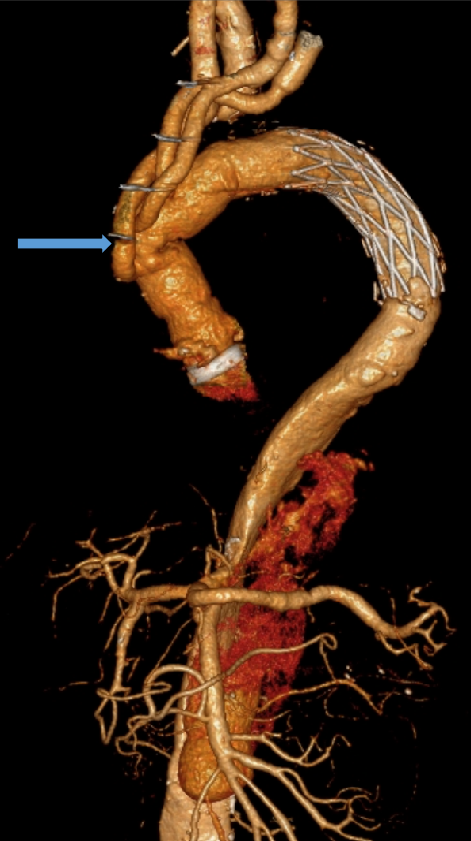

病例:复杂TAAD多次手术后,IIIc型内漏

术后2年随访:动脉瘤增大、左肾支架脱出